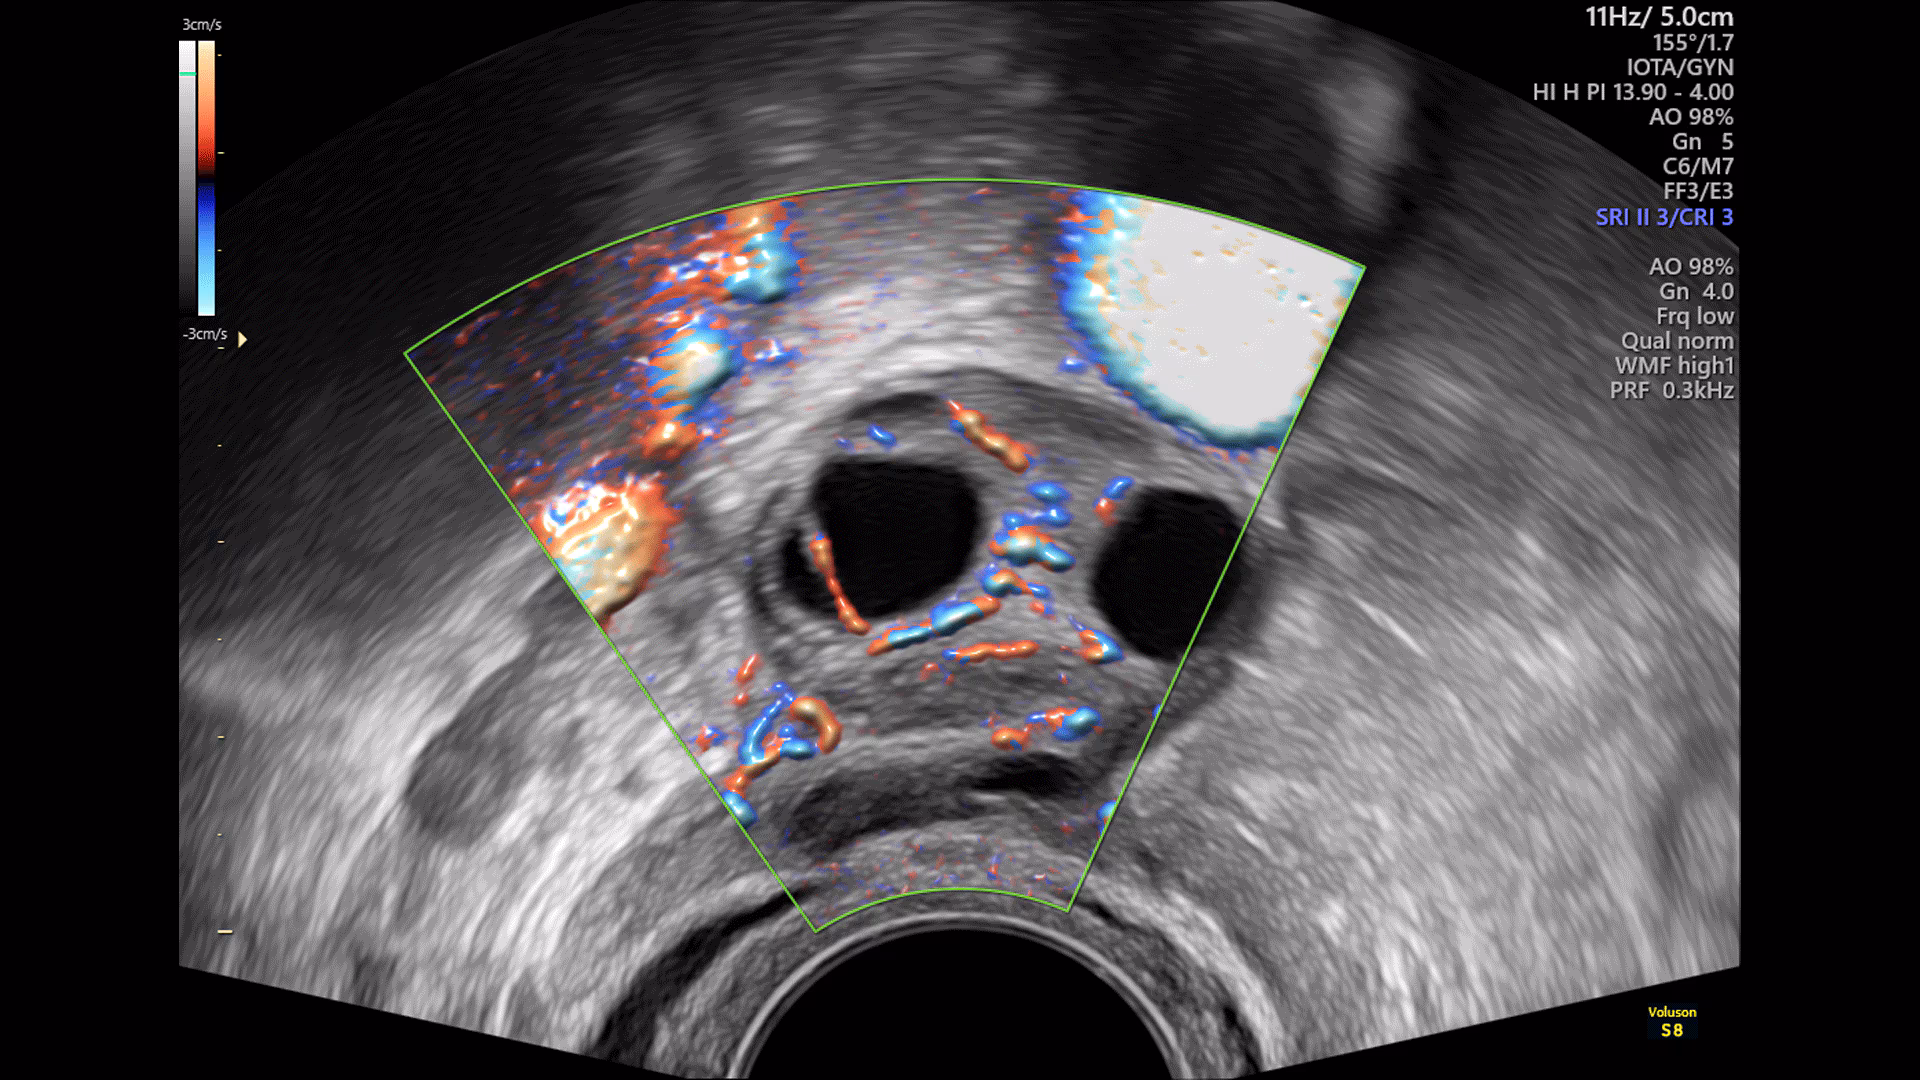

Sistema ecografico per ostetricia, ginecologia e fertilità

VOLUSON S8 con Touch panel

- 3D Uterine Trace

- Immagini veloci chiare e uniformi

- Dettaglio e risoluzione di contrasto eccezionale

- Visualizzazione dei piccoli vasi e dei bordi nel cuore fetale con RadiantFlowTM

- HDlive: tecnologia di rendering 3D/4D di Voluson che trasforma i dati ecografici in immagini più realistiche con profondità, illuminazione e texture migliorate